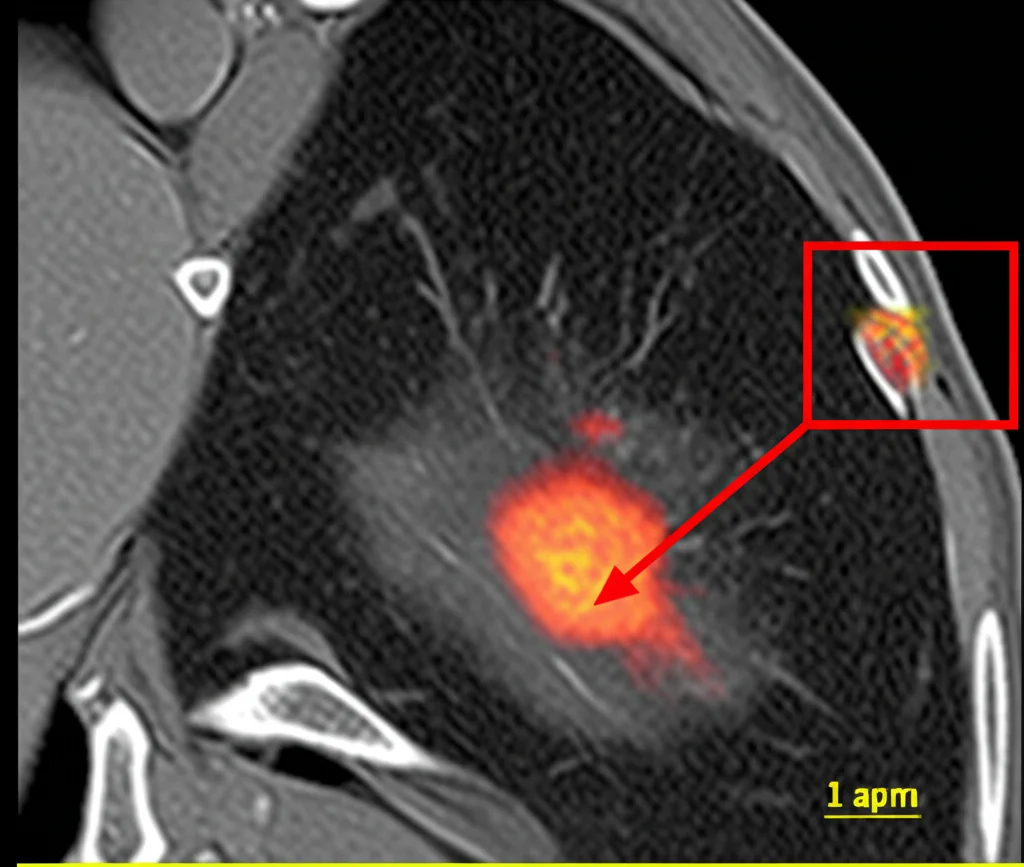

Per rendere i risultati ancora più rilevanti per l’uomo, abbiamo utilizzato un modello murino “umanizzato” (huPBMC-NOG-dKO). In questi topi, che hanno un sistema immunitario parzialmente umano, abbiamo impiantato cellule di TNBC umano (MDA-MB-231) direttamente nel cuscinetto adiposo mammario (impianto ortotopico). Abbiamo poi trattato i topi con posaconazolo.

Monitorando la crescita tumorale con la risonanza magnetica (MRI), abbiamo osservato una marcata riduzione del volume tumorale nei topi trattati con posaconazolo già dopo una settimana. Alla fine dell’esperimento (21 giorni), i tumori nei topi trattati erano significativamente più piccoli. È importante sottolineare che il farmaco è stato ben tollerato, senza effetti collaterali evidenti. Le analisi genetiche (RNA-seq) dei tumori trattati hanno mostrato un potenziamento delle risposte immunitarie mediate da IFNγ e TNFα.